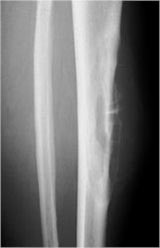

- Diaphyseal lesion on external surface of bone; medullary canal uninvolved

- Radiolucent mass extending into surrounding soft tissues

- Saucerized cortex with chondroblastic soft tissue mass that is usually primarily radiolucent on plain X-rays

- Periosteal reaction usually most evident feature on surface of bone (Hair on End or Sunburst appearance with spiculated pattern of calcification oriented perpendicular to the bone)

- Cortical thickening at margins of erosion (40%)

- Spiculated or sunburst periosteal reaction (due to periosteal elevation)